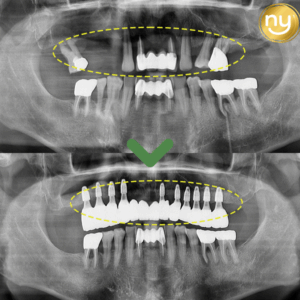

울산안아픈치과 신경치료 후 염증 치아재식술로 해결해요! 안녕하세요. 울산안아픈치과 뉴욕연합치과입니다. 임플란트가 워낙 보편화되고 선호하는 분들이 많아지고 있지만, 자연치아를 살리고자 하는 수요도 급상승하고 있는 추세입니다. 위 환자분은 충치가 많이 진행되어 신경치료한 치아를 사용하고 있었습니다. 하지만, 오랜 기간이 지나 치아 뿌리 끝에 염증이 생겨 발치를 권유받았는데요, 발치를 하더라도 치아 뿌리만 손상 더보기…